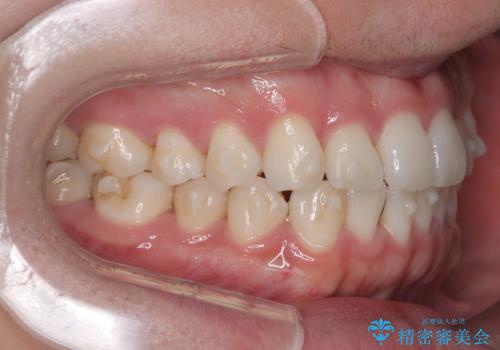

歯のデコボコを治したい|インビザラインで綺麗な歯並びに!|矯正期間は6ヵ月!

- 歯のデコボコが気になるを主訴に来院された患者様です。

インビザラインで歯は抜かずに非抜歯でデコボコを改善しました。

インビザラインで叢生の改善を行いました。

歯は抜かずに、拡大と少しのIPRで並べました。

矯正期間は半年です。

綺麗な歯並びを手に入れ大変ご満足していただきました。